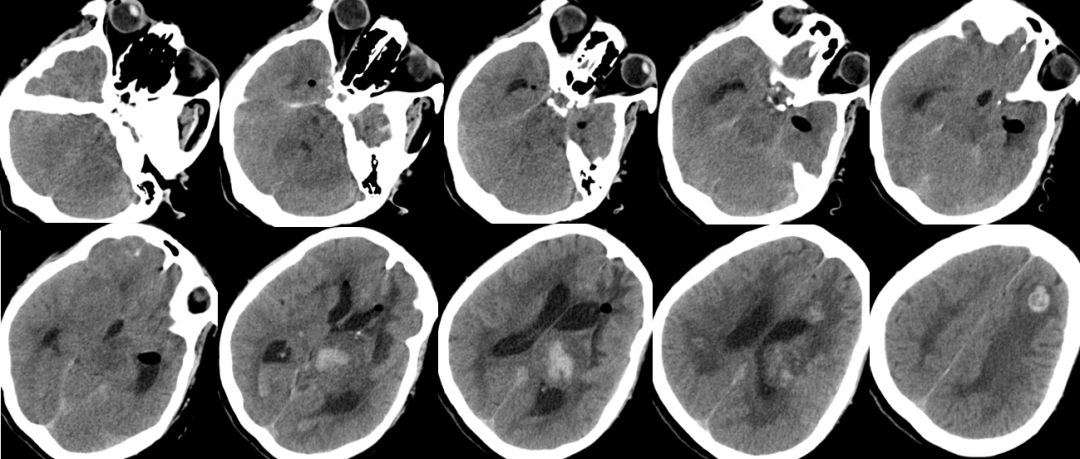

2014-11-18 0am CT

2014-11-18 10am CT

2014-11-19 CT

2014-11-20 CT

再出血?

脑水肿?

脑积水?

腰大池过度引流?(非高颅压脑疝)

肺炎?

2014-11-24 CT

气颅、轻度脑积水,加强脱水,必要时用激素

2014-11-18 CT